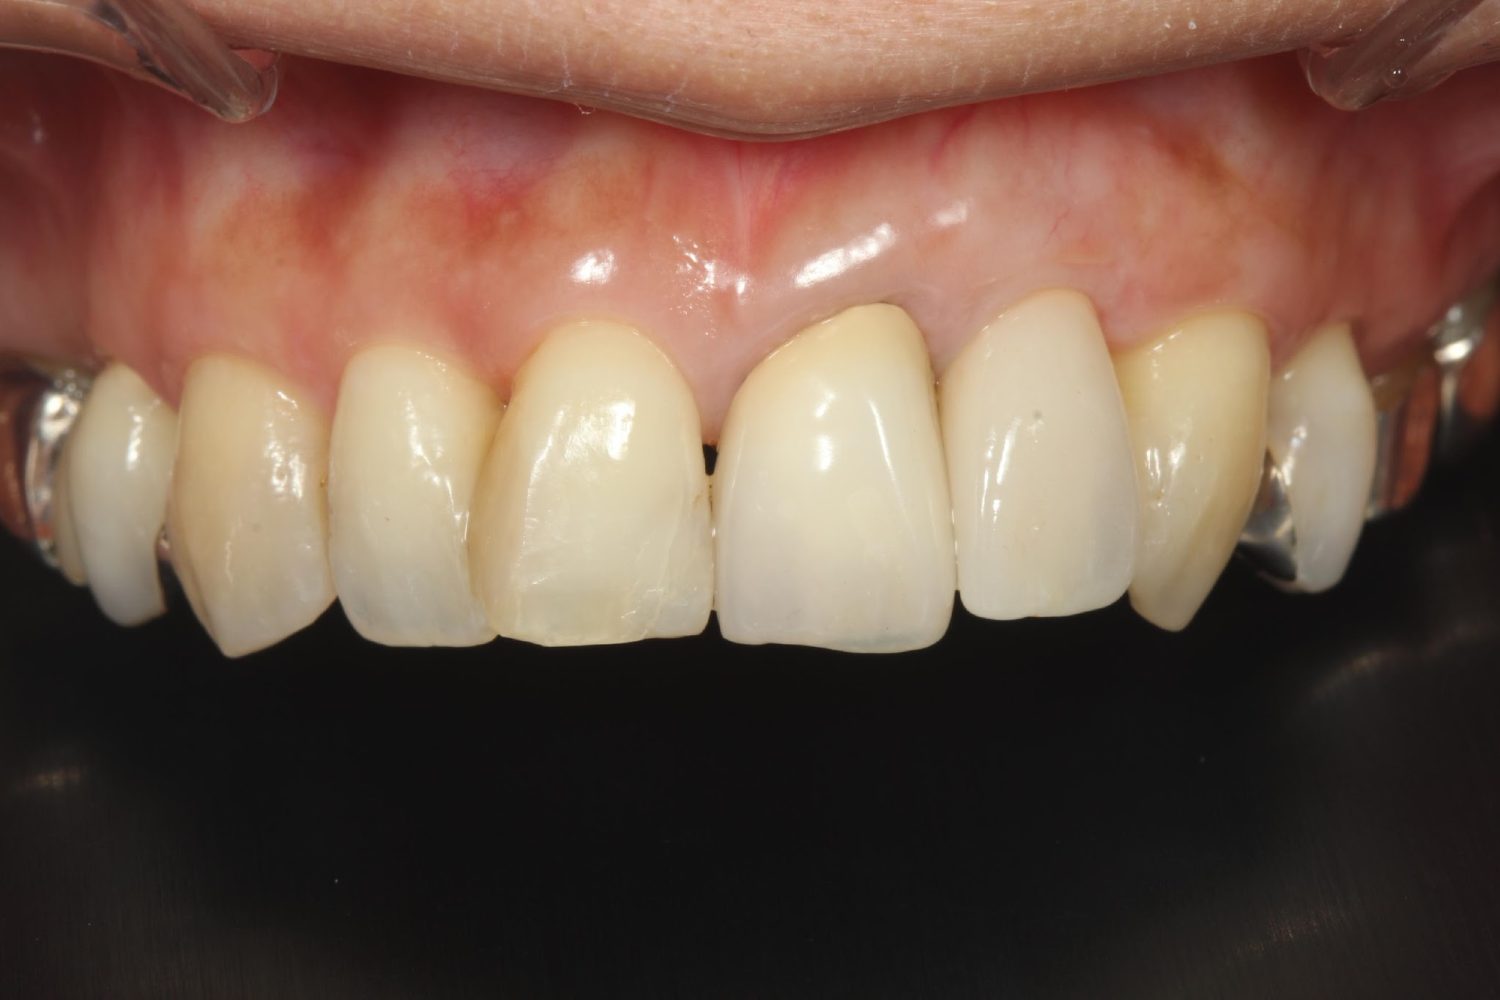

インプラント治療の症例紹介②

Before

After

主訴

前歯の脱落、歯肉の腫れ

治療内容

修復物の脱落時に支台築造のポスト部で歯質を破折。抜歯即時インプラント埋入をおこなったケース。

治療費

473,000 円(税込)

治療期間

8か月

治療回数

12回

想定されたリスク

※経年的な歯肉退縮の恐れ、インプラント周囲炎の恐れがありました。

残存した歯根に感染が少なく、抜歯時即時にインプラント埋入手術を行った。術後〇年経過し安定している状態。